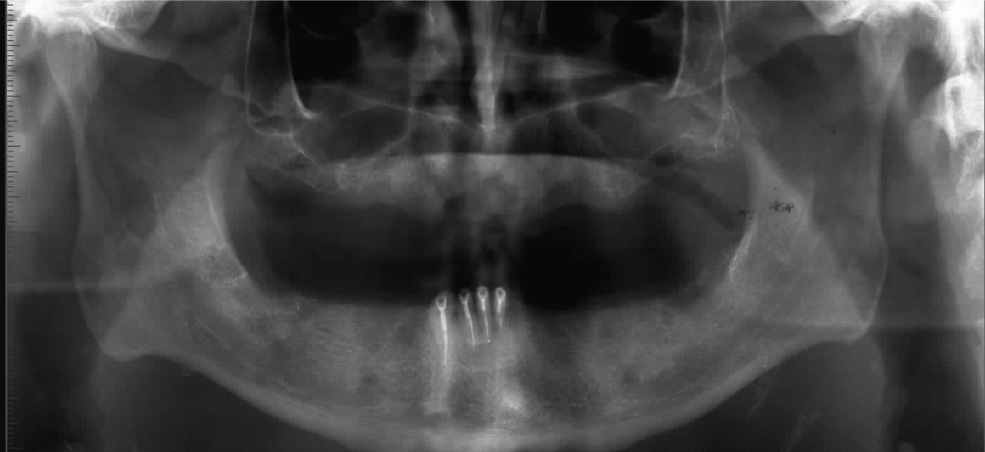

Gli impianti hanno il compito di sostituire uno o più denti mancanti, fino ad un’edentulia completa, e di servire da sostegno per una protesi ad essi ancorata.

Allo Studio Ragazzini sappiamo gestire al meglio il tessuto osseo, che costituisce il sostegno dell’impianto, e siamo in grado di ricostruire tale tessuto nel caso esso venga a mancare, anche in situazioni molto complesse.